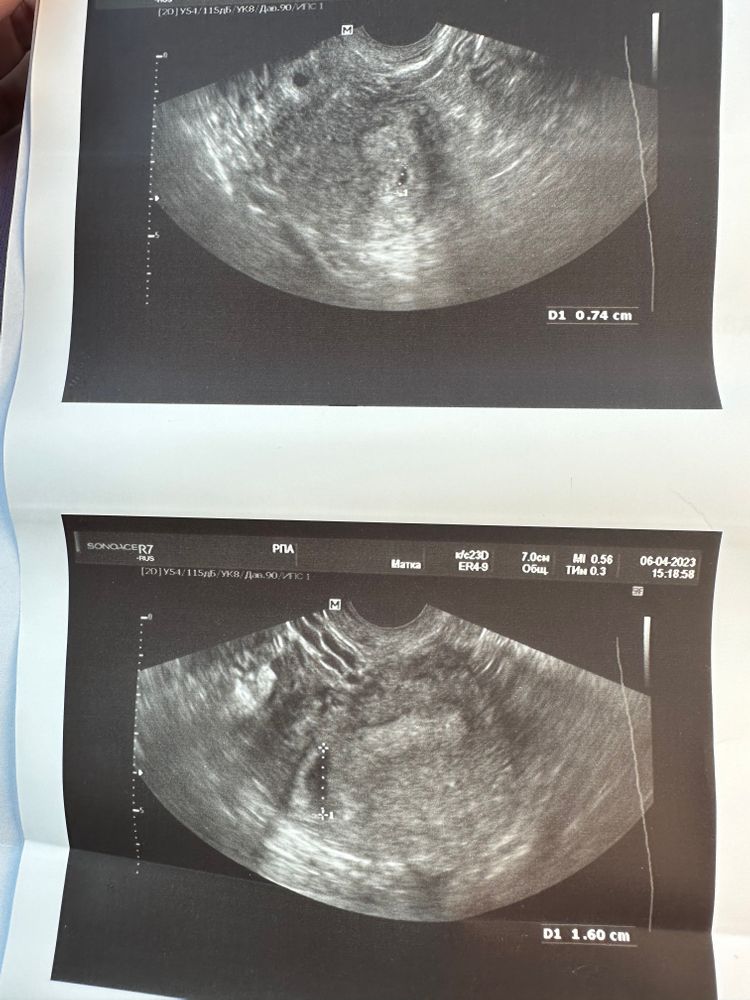

Врач, проводившая УЗИ, в заключении написала: одно плодное яйцо СВД - 0,74 мм, визуализируется ретрохориальная гематома до 16 мм в области дна матки, желтое тело 29х19мм. Порекомендовала ставить дважды в день папаверин и покой.

Иногда так бывает, что на самом деле нет никакой гематомы, просто на очень раннем сроке беременности полость матки еще не сомкнулась полностью, и могут принять за гематому. У вас есть фото узи?

Яна, напишу то что я думаю. Я так поняла первое фото это плодное яйцо. Размер гематомы больше размера плодного яйца, при таком размере у вас давно бы все отслоилось и случился выкидыш. И мне непонятно , как вообще соотносятся друг с другом гематома и плодное яйцо, гематома должна окружать плодное яйцо, а тут оно вообще как будто отдельно.

Поэтому мне кажется , что здесь именно то, что я писала выше.